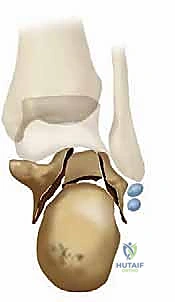

2. التوسع الجانبي والانحشار الشظوي العقباني (Fibulocalcaneal Impingement)

عندما يتهشم عظم العقب، فإنه ينضغط من الأعلى للأسفل، مما يؤدي إلى توسعه وانتشاره نحو الخارج (Lateral Wall Blowout). عندما يلتئم العظم على هذا النحو، يصبح الكعب أعرض بكثير من الطبيعي. هذا الجدار الجانبي المتوسع ينحشر مباشرة ضد الجزء السفلي من عظم الشظية (الكَعب الجانبي - Lateral Malleolus). هذا الانحشار العظمي يسبب ألماً حاداً عند الوقوف والمشي، ويجعل من المستحيل تقريباً ارتداء الأحذية المغلقة.

- اتساع وتشوه شكل الكعب: الكعب يبدو عريضاً ومنتفخاً مقارنة بالقدم السليمة.

- صعوبة بالغة في ارتداء الأحذية: بسبب اتساع الكعب، تحتك الأحذية العادية بالبروز العظمي الجانبي مسببة تقرحات وألماً.